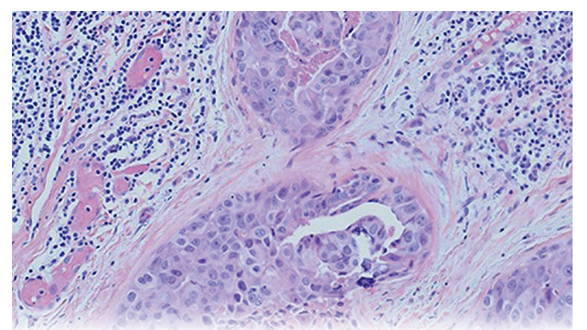

Using Pleomorphic Adenoma Gene 1 (PLAG1) to Distinguish Carcinoma of the Parotid Gland From Primary Lung Cancer: A Case Study

Avigayil East, DNP

March 22, 2023